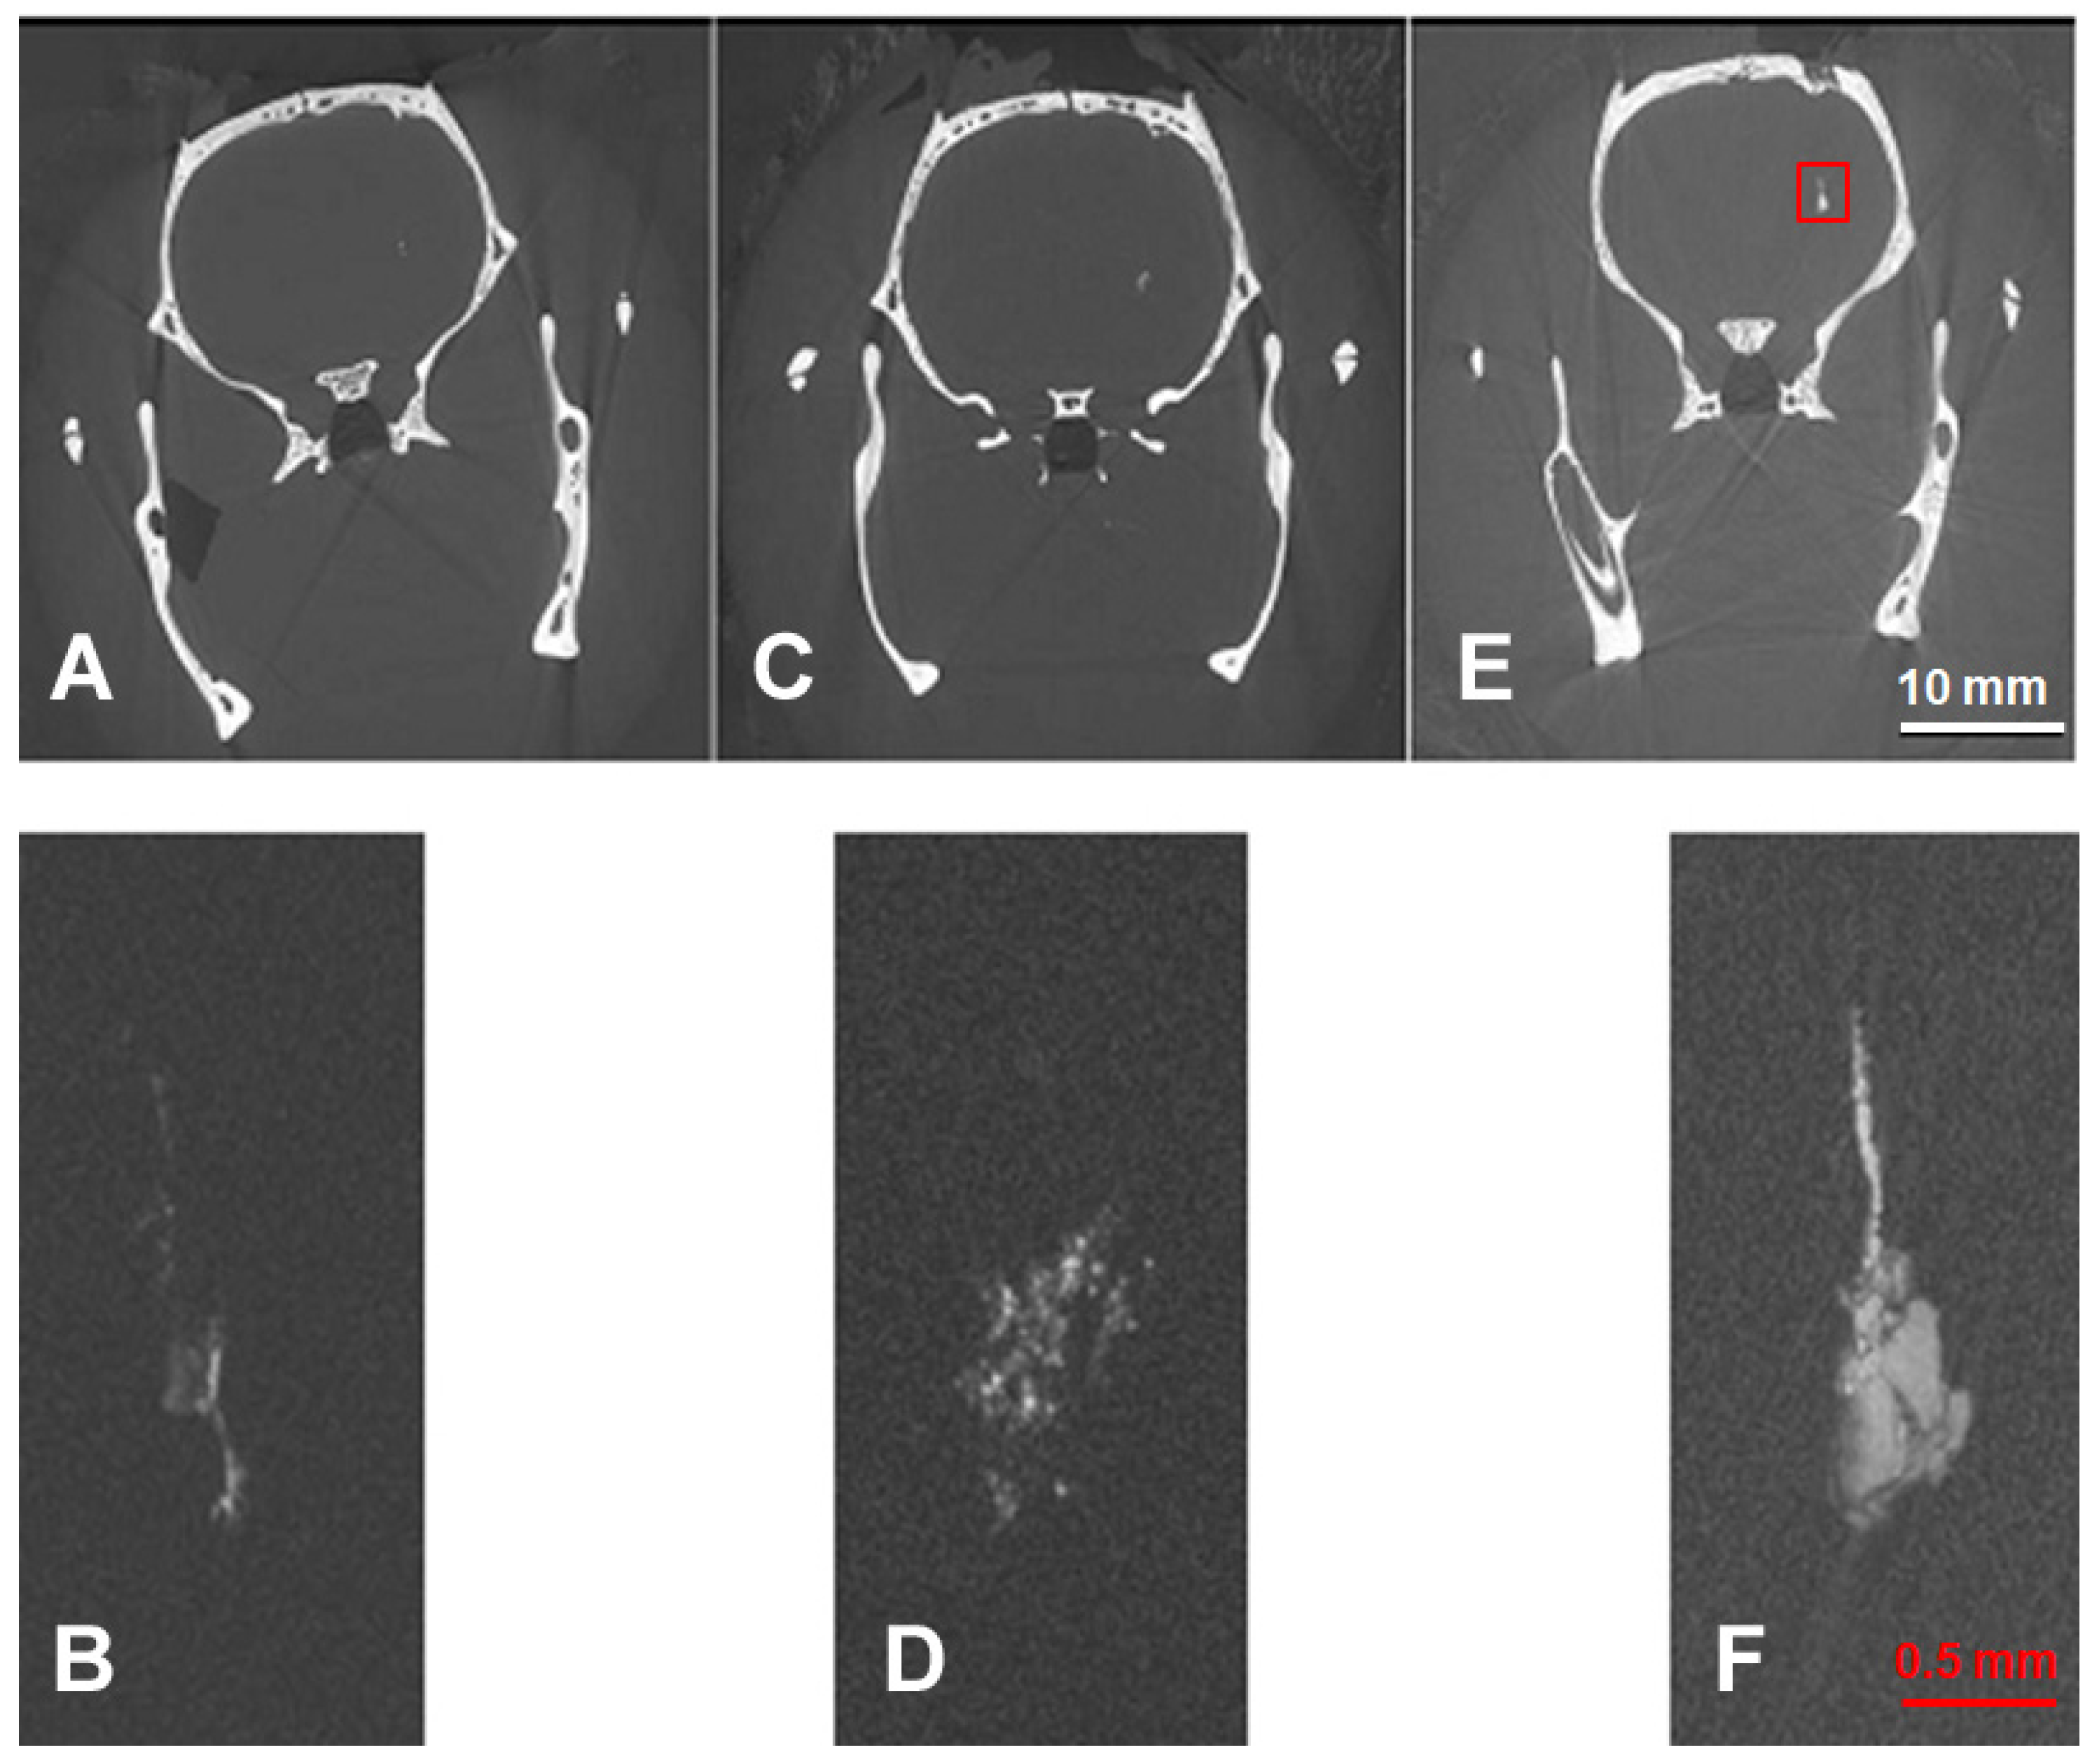

3.1. Comparison of Imaging Modalities